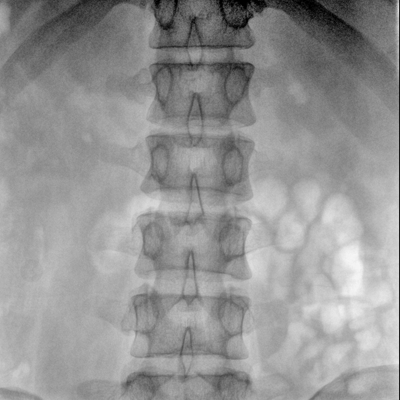

骨科: 经皮锥体成形术、经皮椎间盘臭氧治疗术、胸脊椎固定、骨活检、腰椎内固定术等。